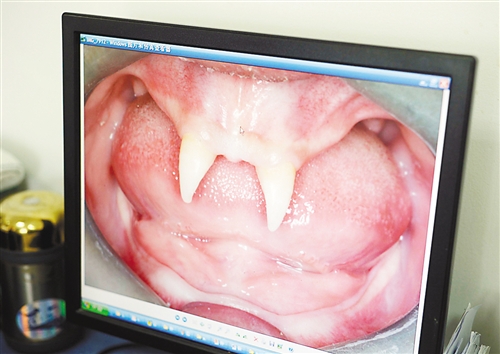

12月18日,16歲的張成(化名)從小到大,只有上顎部分有兩顆牙,看上去更像長著一對獠牙。 記者熊明攝

重慶日報訊 每個人都有牙齒,但對16歲的張成(化名)來說,從小到大,他只有上顎部分有兩顆牙,看上去更像長著一對獠牙,這讓他很自卑又易怒。12月18日,在母親的陪同下,他來到三軍醫(yī)大西南醫(yī)院求助。經(jīng)醫(yī)生檢查,發(fā)現(xiàn)張成患有一種罕見的基因病。

張成是貴州銅仁地區(qū)思南縣人,從生下來就似乎得了一種怪病,身上毛發(fā)稀少,面部發(fā)育也不好。更奇怪的是,別人家的孩子都長牙吃東西了,他卻一直長不出牙齒,最后只在上顎部分冒出兩顆比較突出且對稱的牙齒,看起來就像一對獠牙。